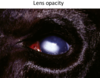

lens opacity

Lens opacity occurs when the carcass is very cold or frozen. The change will reverse to normal transparency on warming, but it can be confused with cataracts in cold carcasses.

水晶體混濁lens opacity:因缺氧導致蛋白質變性,變得混濁可藉由水晶體的混濁程度判斷該動物死亡多久,死亡愈久,水晶體愈混濁。易與cataracts白內障混淆,要判斷為何者仍須透過切片儀器判讀